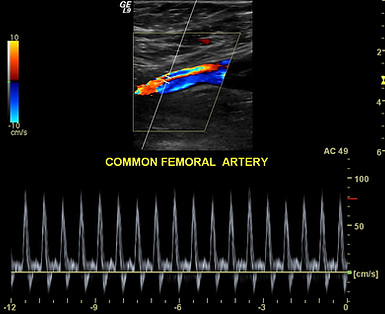

Extremity Arterial (Artery) Ultrasound

Arteries are the blood vessels that carry blood from your heart to a specific organ or body part. Extremity artery ultrasounds evaluate blood flow in the limbs (arms or legs). The goal of these ultrasounds are to determine if there is any plaque buildup or whether a blockage has occurred that would limit the flow going to a body part. The photo above is a leg arterial.